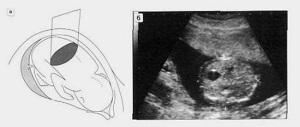

Показатели плода, которые может оценить врач во время второго планового ультразвукового исследования:

1 – лобно-затылочный размер. 2 – бипариетальный размер. |

Бипариетальный размер – поперечный размер головки плода, измеряется между выступающими частями теменных костей (находятся выше височных костей). Размеры в норме, в зависимости от срока беременности: · 16 недель – 3,4 см. · 17 недель – 3,8 см. · 18 недель – 4,3 см. · 19 недель – 4,7 см. · 20 недель – 5 см. · 21 неделя – 5,3 см. · 22 недели – 5,7 см. |

Лобно-затылочный размер – продольный размер головки, измеряется между выступающими частями лобной и затылочной кости. Размеры в норме, в зависимости от срока беременности: · 16 недель – 4,5 см. · 17 недель – 5 см. · 18 недель – 5,3 см. · 19 недель – 5,7 см. · 20 недель – 6,2 см. · 21 неделя – 6,5 см. · 22 недели – 6,9 см. |